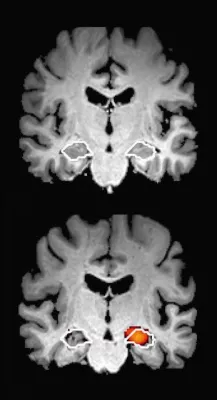

Schon länger ist aus mehreren Studien bekannt, dass kognitive Tests eine Demenz 10-12 Jahre vor den klinischen Symptomen "vorhersagen" können - genauer gesagt: erste Einschränkungen bei Personen erkennen können, die im Alltag noch nicht klinisch auffällig / symptomatisch sind, bei denen aber später einen Demenz diagnostiziert wird. Das amerikanische "Rush Institute for Healthy Ageing" hat unlängst in einer prospektiven Studie an 2125 Personen gezeigt, dass dies sogar 18 Jahre oder noch früher möglich ist.

In der Studie zeigte sich auch, dass ein Verlust der sogenannten "Exekutiv-Funktionen" des Gehirns dem "Gedächtnisverlust" sogar oft noch voraus gingen, und daher ein mindestens gleich gutes Kriterium der Früherkennung sein können. Daher seien multi-dimensionale Tests die mehrere verschiedene Hirnfunktionen inklusive Exekutivfunktionen und Gedächtnis testen, den ein-dimensionalen Test bei der Früherkennung vermutlich überlegen.